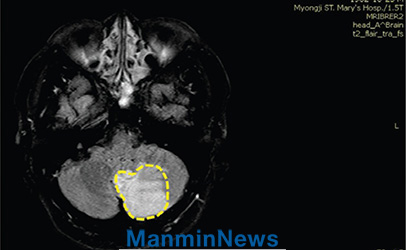

4月10日の朝、ひどい嘔吐があって病院に行ったら、お医者さんは「なんでこんなに遅く来たのですか。脳梗塞で小脳がかなり壊死して、後遺症は避けられないでしょう」と言うのでした。小脳は体の運動機能を調節する役割をしますが、それが壊死したので、私の体にマヒ症状が現れるだろうということでした。私は集中治療室に移され、検査結果を見たお医者さんは「脳の写真では不可能なことなのに、患者さんが話もできるし頭もはっきりしているから、本当に珍しいですね」と言いました。お医者さんは動かしにくいところはないのか、腕と脚から力が抜けたりしびれたりはしていないのか何回も尋ねましたが、そのたびに大丈夫だと言うので、不思議に思ったのです。二日経つと頭痛もなくなって、体が回復して歩くこともできました。

MRI: 左小脳に脳梗塞の所見